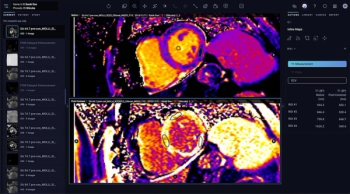

The AI-powered Tempus Pixel software update provides T1 and T2 inline maps to augment cardiac MRI assessment.

In a recent interview, Takeshi Tsuda, M.D., discussed new study findings that show the viability of integrated wall stress as a key diagnostic marker for detecting preclinical cardiomyopathy in patients with Duchenne muscular dystrophy.

For myocardial extracellular volume quantification, single-phase and dual-phase photon-counting CT provided over 20 percent higher correlation with cardiac MRI in contrast to dual-phase energy-integrating detector CT, according to new research findings.